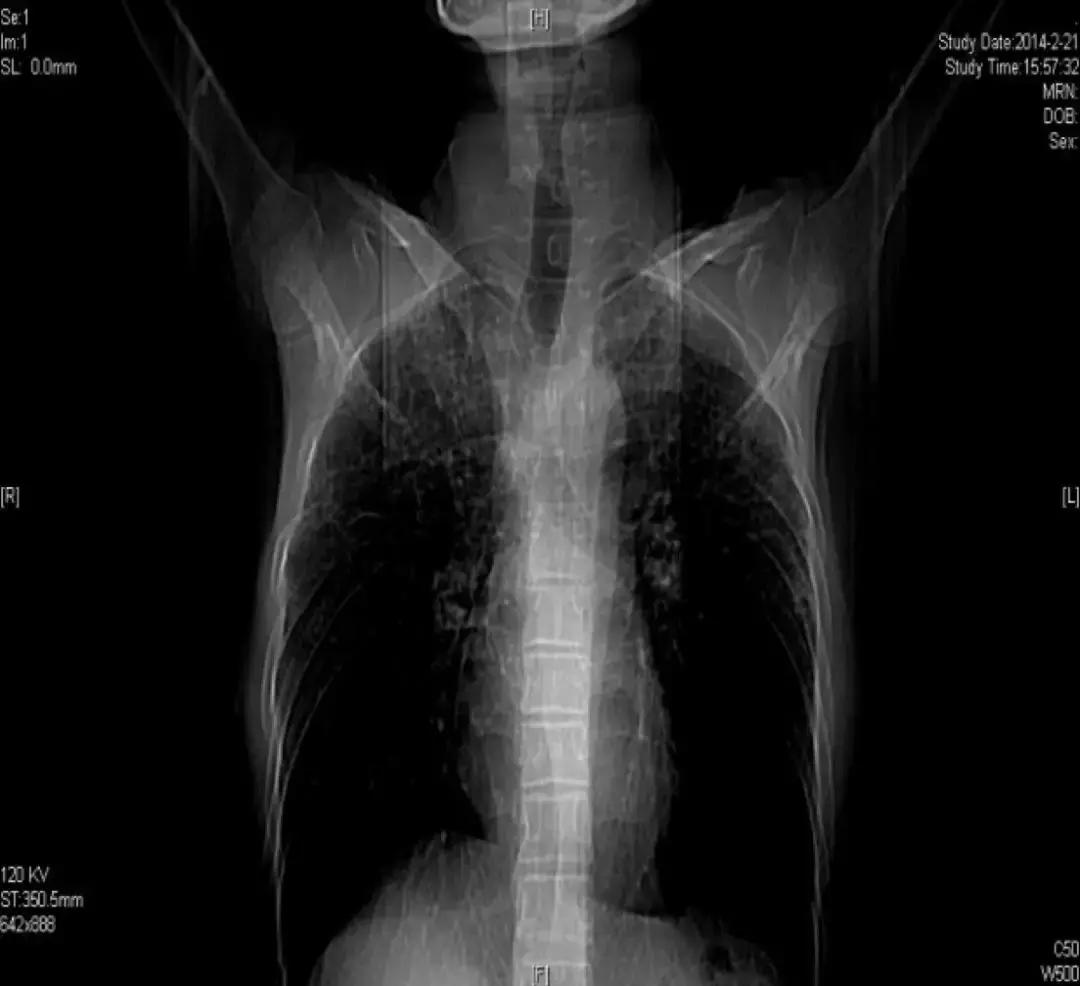

胸部正位片(2018-03-01):

胸部正位片(2018-06-01):最后一次

由于儿子反复治疗的花销已经很大了,这位患者诊断后没有特别治疗,曾去过多家医院,考虑过肺移植,但由于是遗传性疾病只好作罢。随后在我院随访,呼吸困难逐渐加重,间质改变越来越严重,原来是上肺比较明显,后来下肺病变也加重了,再后来右上肺出现大泡,最后出现气胸,反复住院,这个患者后来再也没有来了……